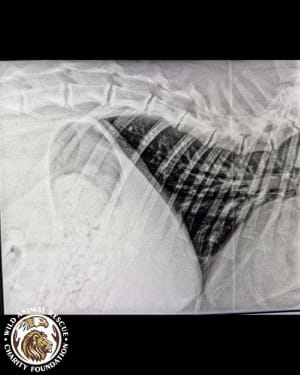

Тварині лише рік, але вона вже стала глибоким інвалідом. Тигриця не здатна самостійно підвестися і ледве пересувається, спираючись виключно на передні лапи. Після ретельного обстеження ветеринари були шоковані станом кісток молодого хижака.

• Критична атрофія м’язів та рахіт.

• Дегенеративні зміни у хребетному стовпі.

• Загальна деформація кісток скелета.

• Двобічна дисплазія кульшових суглобів.

• Остеоартроз та патологічне ремоделювання головки стегнової кістки.